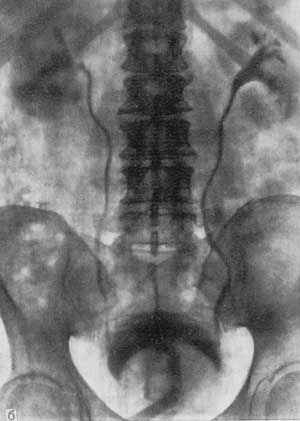

Двухсторонний гидроуретронефроз на рентгенограмме

Гидроуретеронефроз - расширение мочеточника, лоханки и чашечек с постепенным снижением функции почек и атрофии паренхимы. Развивается при врожденных (клапан или уретероцеле) и приобретенных обструкциях мочеточников.